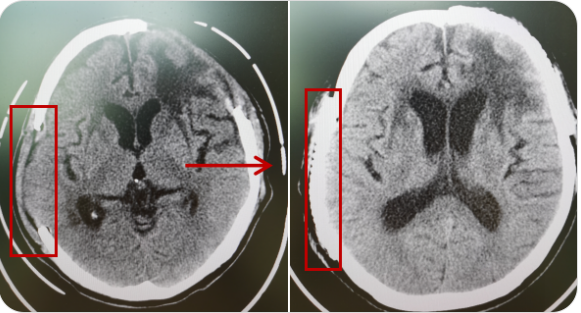

精通顱內(nèi)動脈瘤介入栓塞和手術(shù)夾閉雙技術(shù),系統(tǒng)掌握腦動靜脈畸形、頸內(nèi)動脈海綿竇漏、硬腦膜動靜脈漏等顱內(nèi)血管疾病的診療和手術(shù),精通頸動脈、椎動脈狹窄的血管內(nèi)重建技術(shù),以及頸動脈狹窄的內(nèi)膜剝脫手術(shù)技術(shù)。在顱內(nèi)腫瘤、椎管內(nèi)腫瘤、顱腦損傷、高血壓腦出血等疾病的診治和手術(shù),腦功能性疾病立體定向手術(shù)治療等方面也積累了豐富的經(jīng)驗。

擅長腦血管病(出血與缺血)的神經(jīng)介入與微創(chuàng)手術(shù),能熟練開展腦外傷、重度顱腦損傷的救治工作。